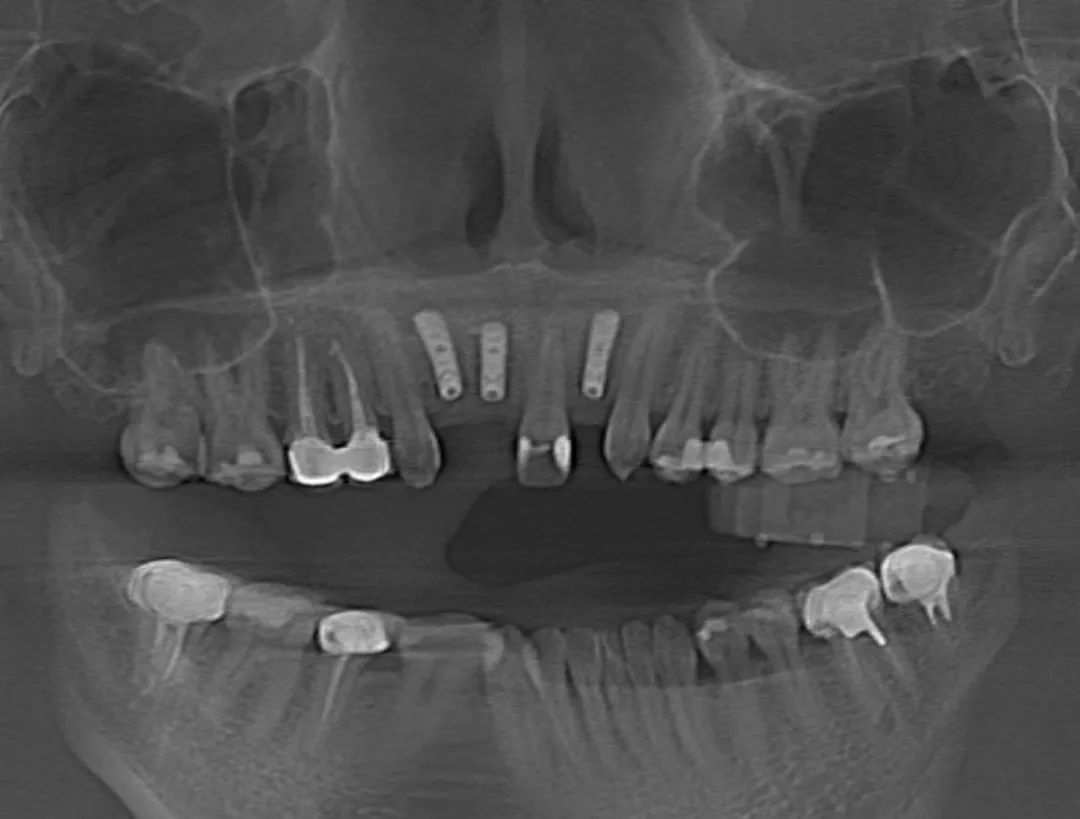

7月15日,瑞金醫(yī)院高益鳴主任團(tuán)隊(duì)實(shí)施了一例口腔手術(shù)機(jī)器人輔助下的上前牙美學(xué)區(qū)種植手術(shù),這是上海首例機(jī)器人輔助下的口腔種植手術(shù)。接受該手術(shù)的患者是一位年輕女性,她因意外事故導(dǎo)致前牙缺失,迫切希望能夠重拾笑容。高益鳴主任詳細(xì)了解她的病史及美學(xué)訴求,決定采用數(shù)字化技術(shù),為她訂制個(gè)性化種植方案。以往,前牙美學(xué)區(qū)的種植及修復(fù)只能依靠醫(yī)生的臨床經(jīng)驗(yàn),簡(jiǎn)單來講就是“手感”,但前牙美學(xué)區(qū)對(duì)術(shù)者技術(shù)要求極高,若是出現(xiàn)毫米級(jí)偏差,就無法達(dá)到理想的粉白美學(xué)(修復(fù)后的牙冠和牙齦美學(xué)指數(shù))效果,還會(huì)導(dǎo)致牙齦萎縮、種植體頸部暴露等諸多問題。口腔手術(shù)機(jī)器人對(duì)此提出了新的解決方案,它可以通過術(shù)前可視化體外模擬,術(shù)中精準(zhǔn)定位、動(dòng)態(tài)導(dǎo)航、人機(jī)隨動(dòng)等功能,極大提升種植手術(shù)的精度和質(zhì)量。醫(yī)生可以借助口腔手術(shù)機(jī)器人,精準(zhǔn)完成口腔種植手術(shù),縮短手術(shù)時(shí)間,實(shí)現(xiàn)標(biāo)準(zhǔn)化種植。

術(shù)前,醫(yī)生將患者的影像學(xué)資料導(dǎo)入機(jī)器人系統(tǒng),進(jìn)行種植體植入全過程的體外可視化模擬,這樣手術(shù)團(tuán)隊(duì)能充分了解患者牙槽骨的骨量及解剖結(jié)構(gòu)走向,更詳盡地制訂手術(shù)方案。術(shù)中,高益鳴主任、李小曼醫(yī)生共同按既定方案,在機(jī)器人全自動(dòng)模式下,精準(zhǔn)標(biāo)定種植位點(diǎn)并逐級(jí)擴(kuò)孔備洞。而且,機(jī)械臂的減速區(qū)設(shè)定,讓機(jī)器人在入口時(shí)動(dòng)作不會(huì)過快,“溫柔”且“迅速”地有序按照指令進(jìn)行手術(shù)。手術(shù)過程相比傳統(tǒng)方式來說縮短了近一半。如今,這位女士恢復(fù)良好。

其實(shí),手術(shù)過程中,患者頭部肯定會(huì)有輕微移動(dòng),而此次使用的“瑞醫(yī)博”口腔手術(shù)機(jī)器人(Remebot Dental Robot)是首款獲國家藥品監(jiān)督管理局(NMPA)認(rèn)證的口腔領(lǐng)域手術(shù)機(jī)器人,它具備的機(jī)器人隨動(dòng)功能,可以檢測(cè)患者位移,保證下鉆過程中軸向準(zhǔn)確性,加上虛擬影像空間和實(shí)際機(jī)器人空間的映射匹配,實(shí)現(xiàn)手術(shù)信息實(shí)時(shí)共享,確保預(yù)備窩洞及植入植體精確至毫米級(jí)水平,使手術(shù)精度控制在1°和0.5mm以內(nèi)。隨著數(shù)字化口腔的發(fā)展,口腔治療將會(huì)迎來更多可能,成為實(shí)現(xiàn)精準(zhǔn)、微創(chuàng)、智能化醫(yī)療的重要組成部分。